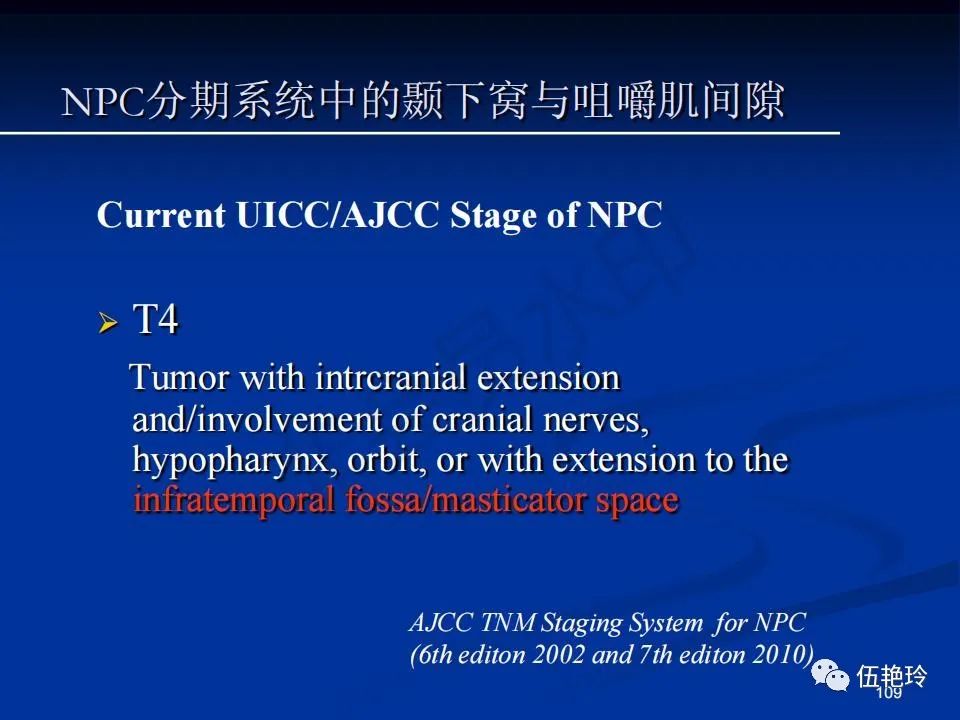

颞下窝与咀嚼肌间隙